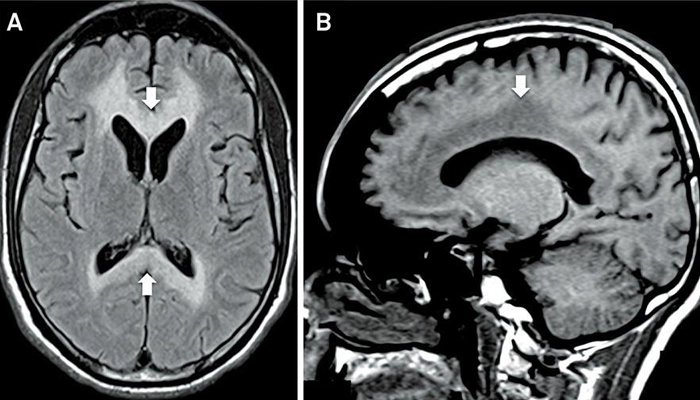

Hình ảnh MRI não trong bệnh Marchiafava-Bignami

Bệnh Marchiafava-Bignami thường được chia thành hai thể chính dựa trên biểu hiện lâm sàng và hình ảnh MRI:

Thể A (cấp tính): Khởi phát nhanh với các triệu chứng nặng như rối loạn ý thức, hôn mê, co giật. Hình ảnh MRI cho thấy tổn thương lan tỏa toàn bộ thể chai. Tiên lượng thường nặng.

Thể B (bán cấp/mạn tính): Triệu chứng nhẹ hơn, chủ yếu là suy giảm nhận thức, rối loạn hành vi. Tổn thương trên MRI thường khu trú một phần thể chai. Tiên lượng tốt hơn nếu điều trị sớm.

Dấu hiệu “sandwich sign” trên MRI là hình ảnh lớp giữa của thể chai tăng tín hiệu, trong khi hai lớp ngoài được bảo tồn tương đối, tạo hình giống bánh sandwich. Đây là dấu hiệu gợi ý quan trọng trong chẩn đoán bệnh Marchiafava-Bignami.